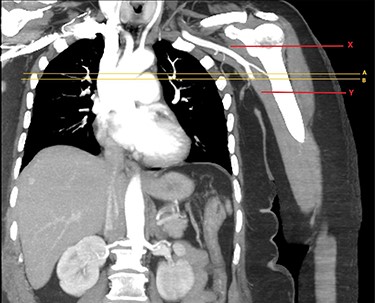

CTA of left upper limb in the coronal plane. X—axillary artery with contrast showing flow as evident in transverse imaging (see Fig. 3), patent in the transverse plane marked A. Flow ceases approximately at the level of the plane marked B. Y—axillary artery occluded as shown with contrast absent.